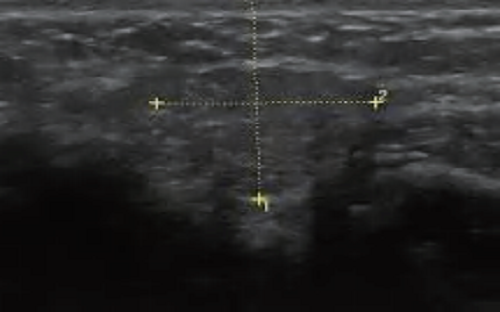

PAU2C aesthetic skin ultrasound device is portable and easy to use for aesthetic medicine. Handheld design allows aesthetic physicians to perform ultrasound whenever patients are in need. Aesthetic medicine ultrasound device works for medical beauty, clinic, hospitals, beauty salon. Our medical beauty ultrasound device that connects with WIFI without restrictions of wiring. Support windows, android, and IOS. Supported ultrasound exam presets for cosmetic medical services include fat factor, HA, PCL, CaHA, PLLA and PDLLA.

PAU2C is a game-changing ultrasound device for aesthetic and medical professionals, combining intuitive usability with advanced features to meet modern clinical and beauty workflow demands. Whether used to evaluate fat distribution, track filler efficacy, or assess tissue response, PAU2C delivers the precision, speed, and dependability professionals need for exceptional patient outcomes.

PAU2C redefines portability and user-friendliness in dermatological ultrasound. Its compact handheld design breaks bulky equipment constraints, enabling aesthetic physicians to provide on-demand skin ultrasound assessments during consultations, follow-ups, or on-site services. This flexibility makes it indispensable across settings: medical beauty clinics, private practices, hospitals, and high-end beauty salons—adapting seamlessly without compromising accuracy or performance.